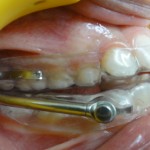

Vue de Gauche

L’appareil est fait d’un système de gouttières et d’activateurs : ce sont les bielles présentes de chaque côté.